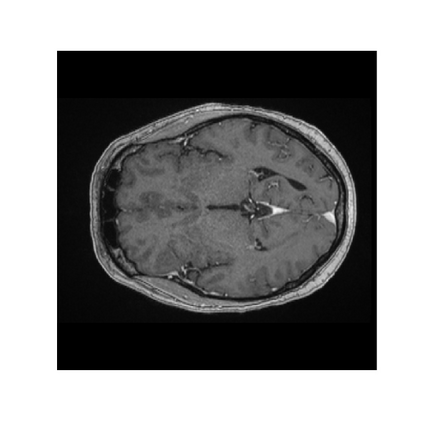

Objectives: Present a novel deep learning-based skull stripping algorithm for magnetic resonance imaging (MRI) that works directly in the information rich k-space. Materials and Methods: Using two datasets from different institutions with a total of 36,900 MRI slices, we trained a deep learning-based model to work directly with the complex raw k-space data. Skull stripping performed by HD-BET (Brain Extraction Tool) in the image domain were used as the ground truth. Results: Both datasets were very similar to the ground truth (DICE scores of 92\%-98\% and Hausdorff distances of under 5.5 mm). Results on slices above the eye-region reach DICE scores of up to 99\%, while the accuracy drops in regions around the eyes and below, with partially blurred output. The output of k-strip often smoothed edges at the demarcation to the skull. Binary masks are created with an appropriate threshold. Conclusion: With this proof-of-concept study, we were able to show the feasibility of working in the k-space frequency domain, preserving phase information, with consistent results. Future research should be dedicated to discovering additional ways the k-space can be used for innovative image analysis and further workflows.